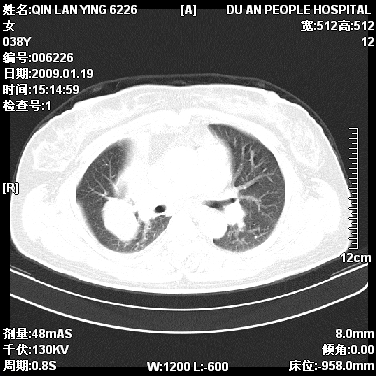

女,38岁,胸疼1个月。wbc:1万4

考虑----右肺中心型肺癌---阻塞性肺炎-----纵膈淋巴结及胸膜转移----肝脏转移

右肺中心型肺癌纵膈淋巴结转移,肝脏转移。右侧胸腔少量积液。

1)右肺中央型肺癌并右肺上叶阻塞性肺炎、节段性肺不张,纵隔淋巴结转移、右侧胸膜转移、肝脏转移。2)右侧胸腔少量积液。

1、右侧中央型肺癌并阻塞性肺不张,纵隔内、主动脉弓旁、右肺门淋巴结及肝脏转移可能性大,建议纤支镜进一步检查。

2、右侧胸腔积液。

本病例有几个容易诊断的地方:1、右肺上叶前段支气管闭塞,肺不张。2、淋巴结明显肿大。3、肝脏多个类圆形低密度影呈“牛眼征”改变,高度提示转移。

从影像学角度分析      右肺上叶中央型肺癌,并阻塞性不张、肺炎,纵隔淋巴结、膈顶淋巴结转移。

肝内两个大小不等低密度结节,内可见更低密度影,首先考虑肝内转移瘤,但联想到患者wbc1万4,建议楼主还是做个增强比较明确,除外肝脓肿的可能。